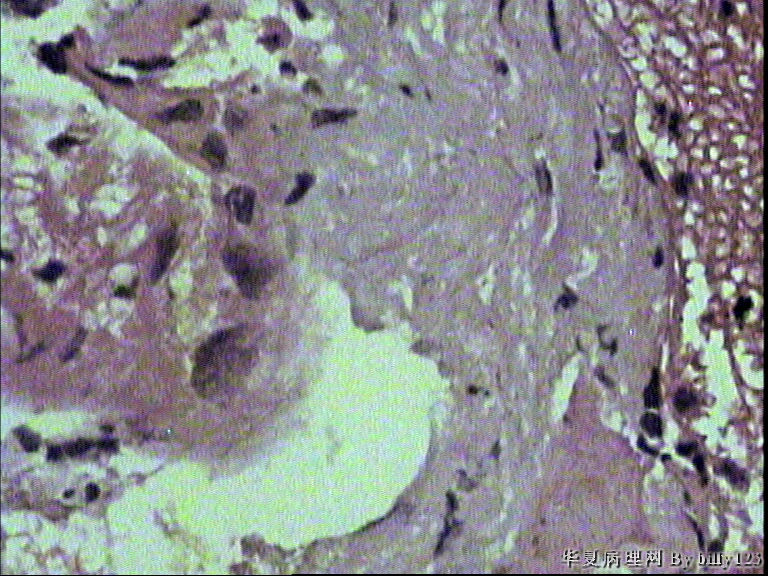

纤支镜活检,女性,75岁,请各位老师指教!

图1